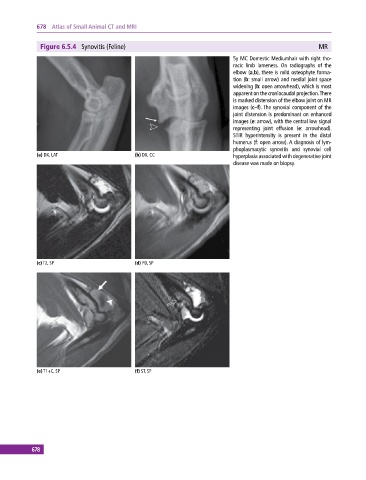

Figure 6.5.4 Synovitis (Feline) MR

5y MC Domestic Mediumhair with right tho-

racic limb lameness. On radiographs of the

elbow (a,b), there is mild osteophyte forma-

tion (b: small arrow) and medial joint space

widening (b: open arrowhead), which is most

apparent on the craniocaudal projection. There

is marked distension of the elbow joint on MR

images (c–f). The synovial component of the

joint distension is predominant on enhanced

images (e: arrow), with the central low signal

representing joint effusion (e: arrowhead).

STIR hyperintensity is present in the distal

humerus (f: open arrow). A diagnosis of lym-

phoplasmacytic synovitis and synovial cell

(a) DX, LAT (b) DX, CC hyperplasia associated with degenerative joint

disease was made on biopsy.

(c) T2, SP (d) PD, SP

(e) T1+C, SP (f) ST, SP